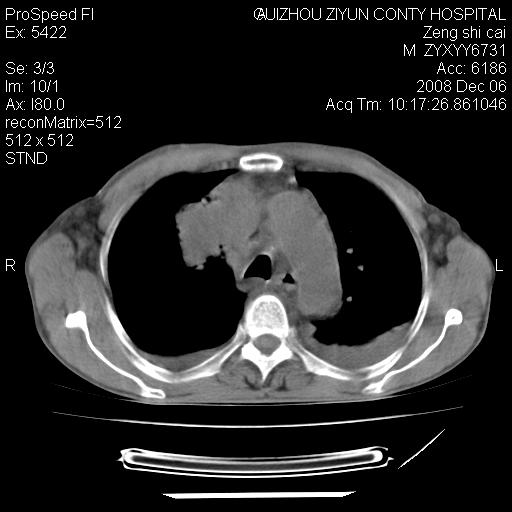

标题: CT16961:M、71岁,咳嗽半年,无血痰;胸片示右肺占位。 [打印本页]

标题: CT16961:M、71岁,咳嗽半年,无血痰;胸片示右肺占位。

右肺癌并纵隔淋巴结及胸膜转移可能性大

右肺癌并纵隔淋巴结及胸膜转移。建议气管镜

右肺纵隔型肺癌伴纵隔淋巴结及胸膜转移!

右肺纵隔型肺癌伴纵隔淋巴结转移!双侧胸水!

1)考虑右肺上叶纵隔型肺癌伴纵隔淋巴结转移。2)心包积液,双侧胸腔积液。

右肺癌并纵隔淋巴转移,腹膜后转移可能性大,两侧胸腔积液

右肺上叶纵隔型肺癌伴纵隔淋巴结转移。心包积液,双侧胸腔积液。

右上肺癌并纵隔淋巴结及胸膜转移。

右肺纵隔型肺癌伴纵隔淋巴结转移!双侧胸水\\心包积液

建议强化!主要鉴别是淋巴瘤与肺癌淋巴结转移。

右肺纵隔型肺癌伴纵隔淋巴结及胸膜转移